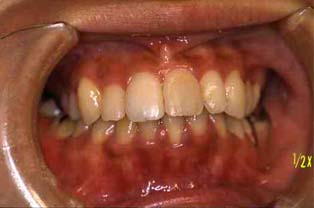

成人その3:八重歯と顎が狭い(唇側低位咬合,歯列狭窄) 22才,女性

歯並びが悪いのが気になって,人前で笑ったりおしゃべりができないようでした。

矯正前

正面

矯正治療後,歯並びもよくなって自信をとりもどした様でした。

矯正前とは違って,人前でも笑ったりおしゃべりしたりして大変明るくなりました!